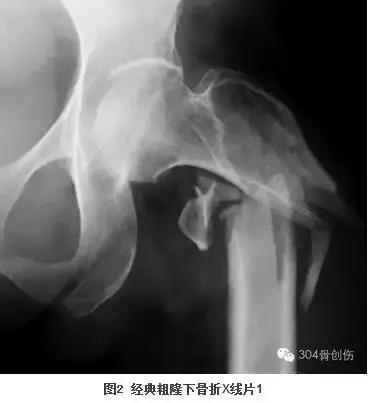

大查房见到一女性病人,57岁,洗澡时地滑导致股骨粗隆下骨折。粗隆下骨折多见于青壮年高能量外伤后,而眼前的病人是一位白净的中年女性,仅仅是洗澡过程中骨折,按说致伤能量不是很高,当时首先想到的是肿瘤骨转移的病理骨折,反复查看X线片和CT后不符合肿瘤骨转移病理骨折。王晓宁主诊医生再次补充病史:患者因内科疾病长期服用激素。服用激素能够导致骨坏死和骨质疏松,骨坏死常见于股骨头,骨质疏松骨折多见于股骨近端。带着疑问全科医生仔细阅读影像资料料,此例粗隆下骨折表现的仅是简单骨折(图1),而经典的粗隆下骨折多是粉碎或长螺旋形(图2、3)。全科医生畅所欲言,充分发表各自看法,却不能完美解释上述疑问,按现有医疗水平处理此类骨折不是难事,但解除不了内心的疑惑。经过激烈讨论后,决定暂缓手术、寻找证据、明确骨折原因。大家分头查找文献,两天后再次讨论。